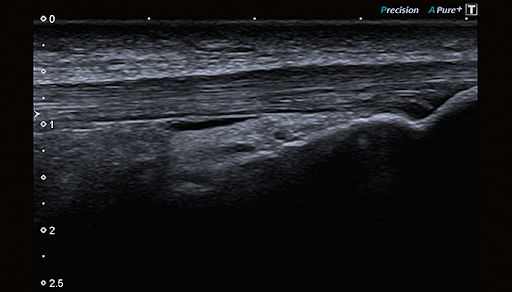

Технологии Precision и Aplipure обеспечивают четкость и детализацию изображений. Эти технологии визуализации предназначены для гармоничной работы, чтобы каждое изображение обеспечивало максимально возможный уровень клинической информации для быстрой и точной диагностики.

Широкий диапазон датчиков, включая доступность высокочастотного изображения до 18 МГц, обеспечивает исключительную четкость и мелкие детали изображения MSK.